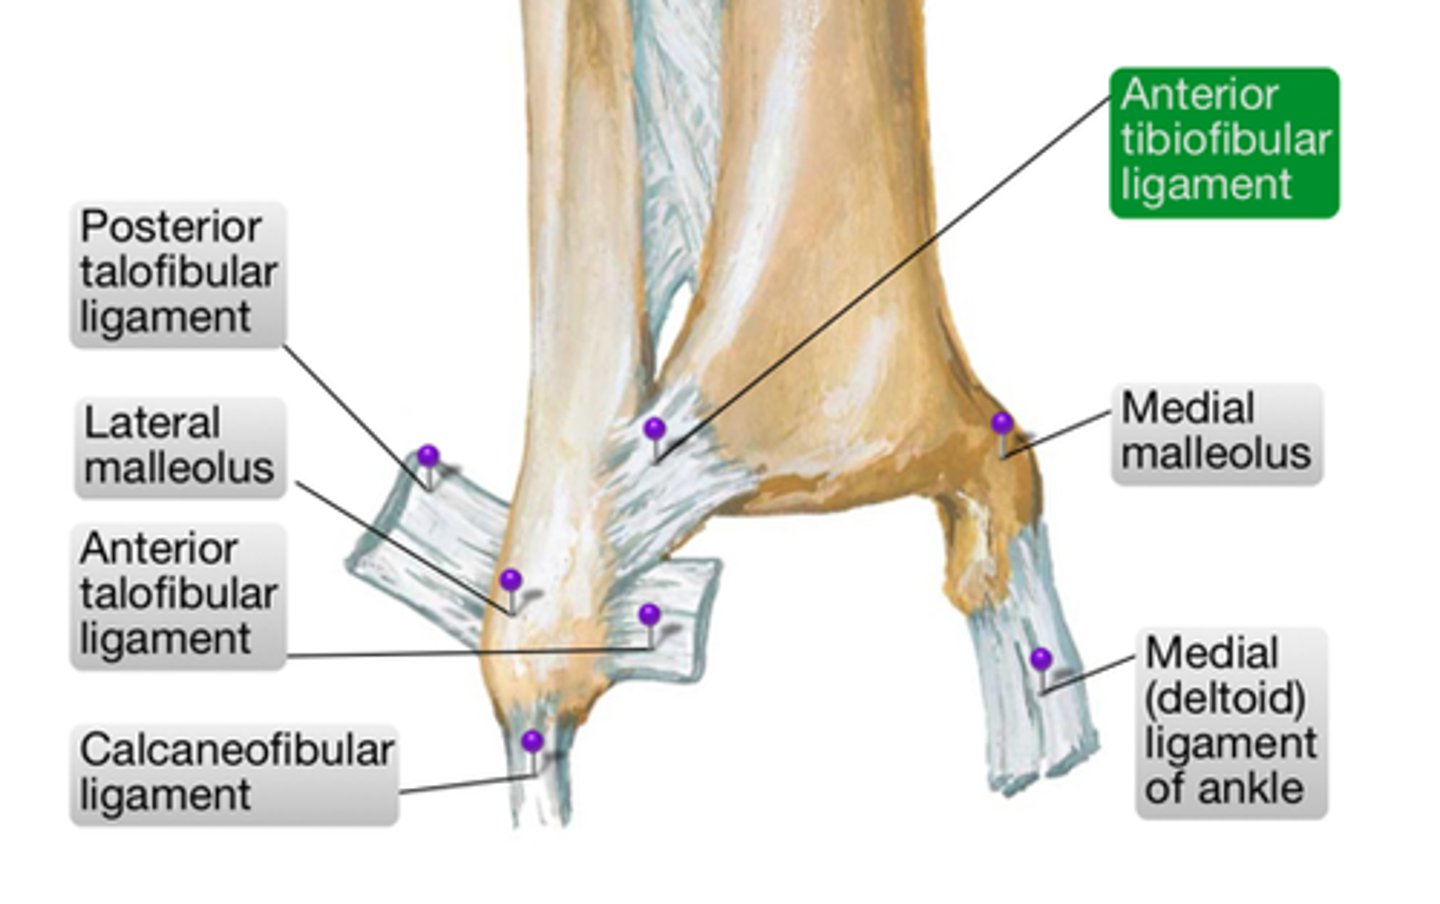

Stability for the distal tibiofibular joint is provided by... (3 structures)

Interosseous ligament

Anterior tibiofibular ligament

Posterior tibiofibular ligament

Function of the deltoid ligament (I function, 3 joints)

Limits eversion at the:

Talocrural joint

Subtalar joint

Talonavicular joint

What ligament stabilizes the talus within the mortise joint?

Posterior talofibular ligament

What ligament limits inversion and dorsiflexion?

Calcaneofibular ligament

What ligament limits inversion and plantarflexion?

Anterior talofibular ligament

Most frequently injured ligament in ankle and foot complex